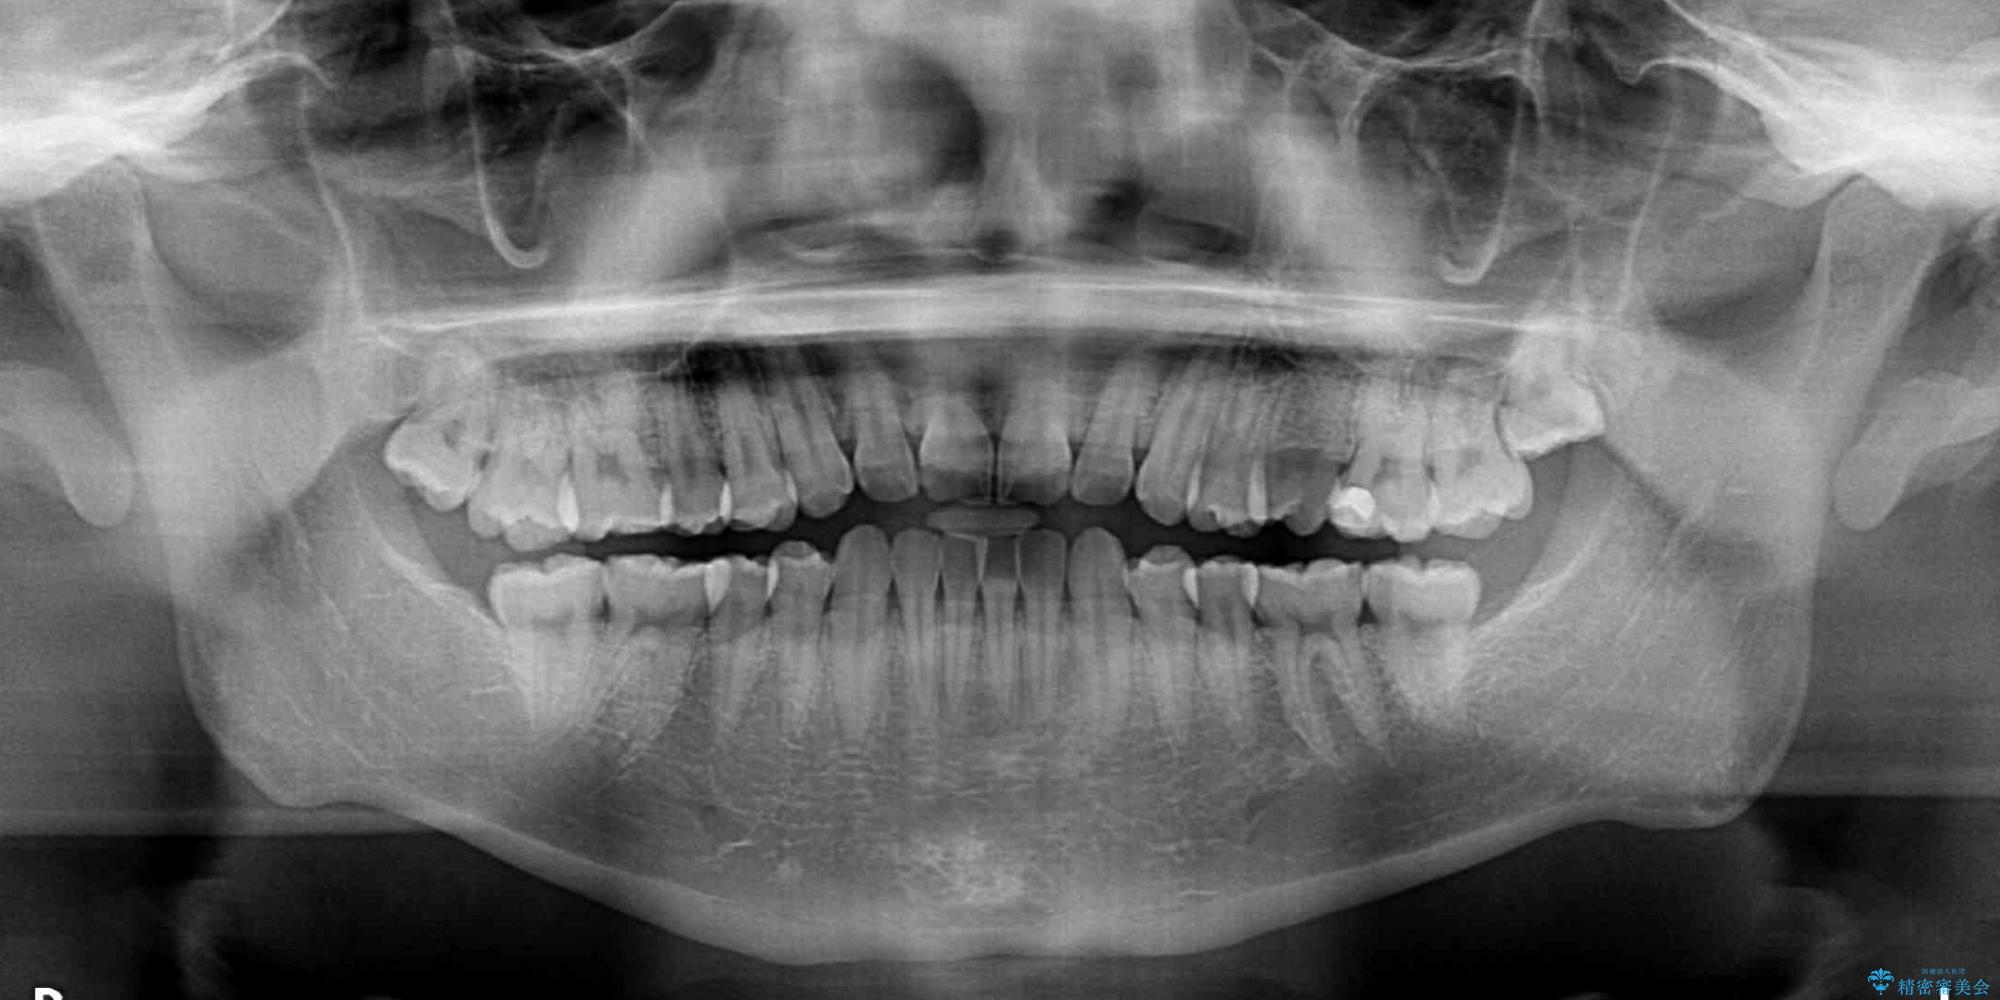

主訴:前歯のデコボコと奥歯のかみ合わせを治したい 今回ご紹介するのは、「前歯のガタガタ(叢生)」と「奥歯のかみ合わせ(シザーズバイト)」にお悩みでご来院された患者様の症例です。 患者様は、 ・歯並びをできるだけ早く改善したい ・費用を抑えた矯正治療 というご要望をお持ちでした。

・上顎左右の第二大臼歯が頬側へ転移し、シザーズバイト(scissors bite)の状態

・上顎左側第二小臼歯が90度捻転しており、噛み合わせに影響

治療前

• 前歯のガタガタ・奥歯のかみ合わせ(シザーズバイト)を改善|1年半で完了したメタルブラケット矯正 治療前画像